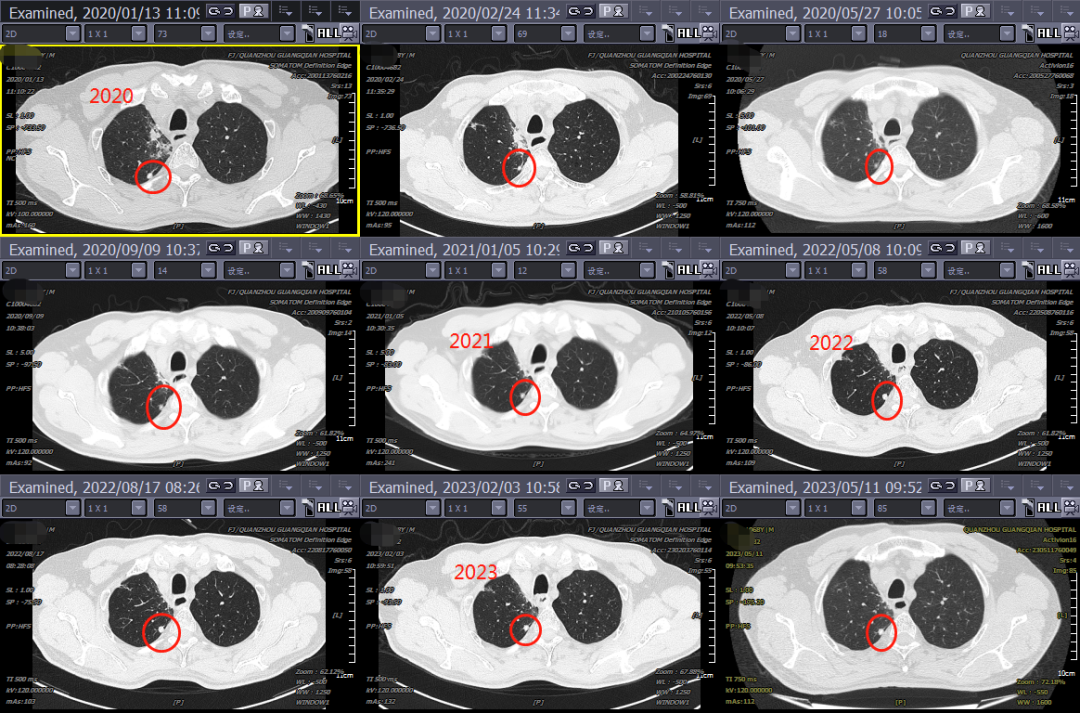

接診病例一

期間,接診了一位被“肺結(jié)節(jié)”困擾多年的患者。孫曉江教授通過將2020年的影像資料與近期的胸部薄層CT進行耐心細致的對比,并在我院腫瘤放療三區(qū)醫(yī)療團隊的共同研討下,判斷為良性結(jié)節(jié)。聽到這個消息后,患者如釋重負,“真的非常感謝你們這么認真專業(yè)地為我診斷!懸著的心終于可以放下來了!”隨即,孫教授為其科普了良性肺結(jié)節(jié)的相關(guān)知識后提出治療建議。